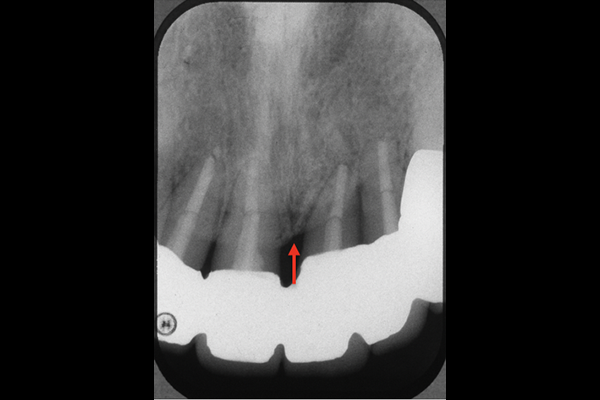

前歯に隙間があいてきている事を主訴に来院されました。検査の結果、歯周病と診断。

歯を残したいと患者さまの強い希望により、マイクロスコープを使用した歯周病治療を行いました。レントゲン写真から赤い矢印部に骨様組織の再生が認められました。

| 主訴 | 歯周病を治したい |

|---|---|

| 治療期間 | 3年 |

| 治療内容 | マイクロスコープを使用した歯周病治療6本 |